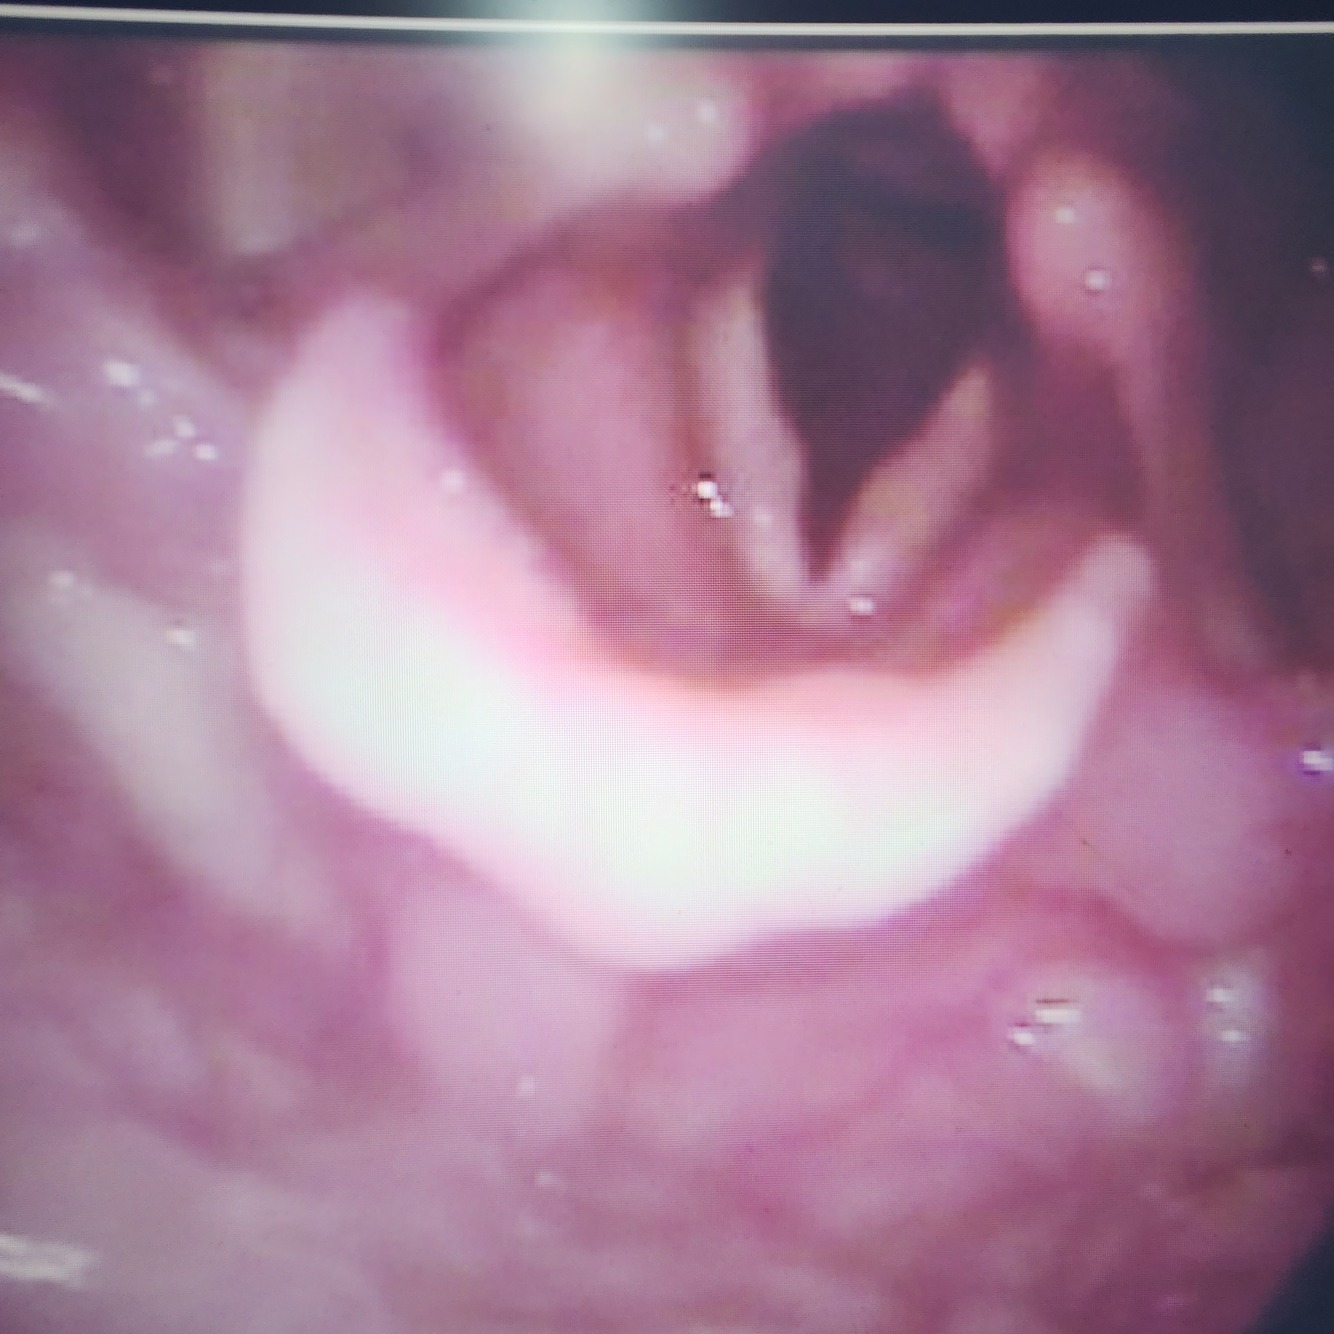

Q

Nomeie as duas estruturas

A

1. Epiglote

2. Valécula